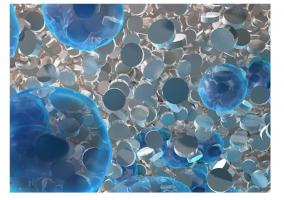

Actualité publiée le 09/06/2022ARTHROSE : Un assemblage prêt à l'emploi pour régénérer le cartilage

Actualité publiée le 22/05/2022